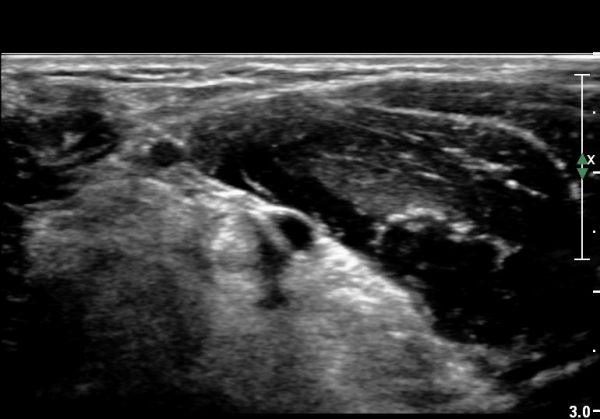

Á¶±Ý ´õ ¸»´ÜÀ¸·Î À̵¿ÇÏ¿© °üÂûÇÏ´Ï ÀÌµÎ¹Ú±Ù°Ç ½ÇÁú³» ÆÄ¿­°ú °üÀý ÁÖÀ§ ¼ö¾×Àú·ù°¡ °üÂûµÊ(±×¸² 4, 5).